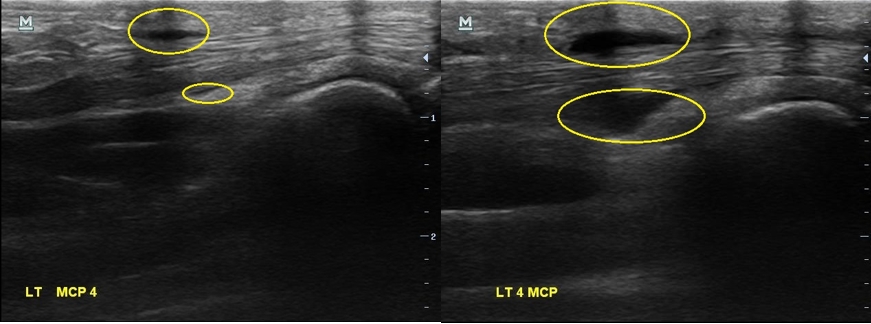

X-ray 검사상에는 특별한건 보이지 않습니다. 초음파 검사에서는.... 4번째 손가락을 굽혀주는 힘줄(4th flexor digitorum tendon)에 염증이 생겨있습니다.

골프에 너무 빠져서 아파도 참고 치셨다는 분... 초음파 검사를 다시 해보니...

2주 전보다 힘줄에 염증이 훨씬 심해져 있었습니다. 그리고

이번에는 한 부위만이 아니라 손가락 굽힘 힘줄을 따라 전체적으로 염증이 퍼져있습니다.